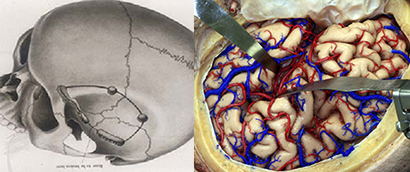

くも膜下出血の原因となる脳動脈瘤(のうどうみゃくりゅう)の外科治療

<画像所見>

左眼の奥に大きな動脈瘤認める。

(→動脈瘤)

<手術方法>

左前頭側頭開頭で動脈瘤クリッピング術を行った。

手術中は脳血管撮影装置を用いたHybrid手術を施行し、動脈瘤の消失を手術中に確認する。

手術中MEP(運動神経)VEP(視力)モニタリングで術後の視力低下や手足の麻痺を予防する。

<実際の手術所見>

<手術中の脳血管撮影画像>

瘤(こぶ)は消失

患者様は術前からあった左視力低下以外に神経症状なし。元気に自宅退院された。